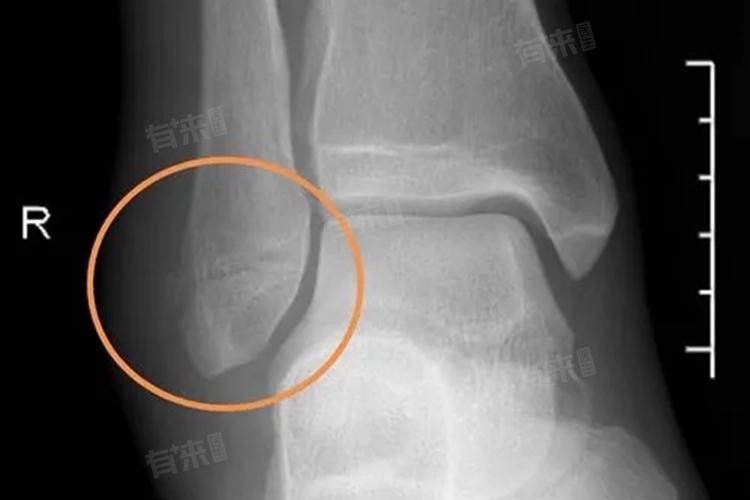

- 在下地活动之前,患者需要通过拍X线片等方式来检查骨折的愈合情况。只有当骨折部位有足够的骨痂生长,且局部比较稳定时,才适合进行下地活动。患者的个人体质、年龄、营养状况以及康复锻炼的积极程度等因素都会影响骨折的愈合速度和下地时间。